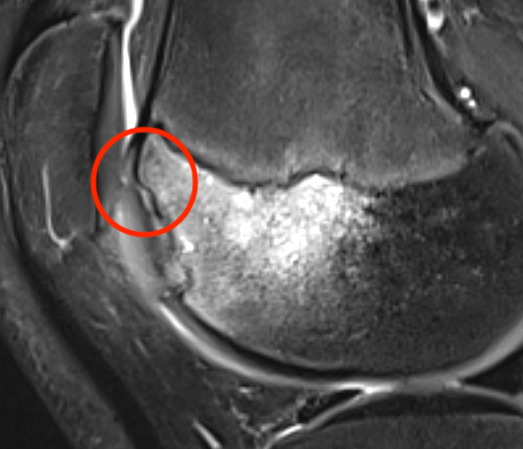

MRI Classification

Stage 3: Articular cartilage breached, high signal indicating synovial fluid behind fragment (unstable)

Stage 4: Loose body (unstable)

Look for

- integrity of the articular cartilage

- fluid behind the lesion, suggesting instability

- displacement of the lesion

Unstable

- cartilage breach with synovial fluid behind lesion

Stage 3. Articular cartilage breach and synovial fluid behind fragment (unstable)

Stage 4. Loose body

Minimally displaced loose body

Completely detached

Location

Medial Femoral Condyle 85%

- lateral aspect of the MFC